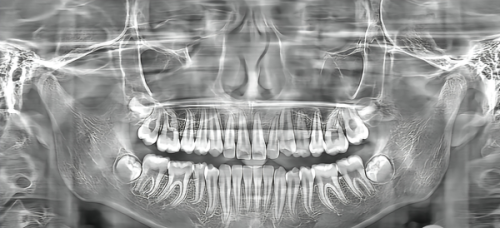

除了专精的医生团队,复兴医院口腔科还配备了精良的医疗设备。数字化口腔扫描仪可以快速、正确地获取口腔的三维数据,为医生制定治疗方案提供严谨的依据。精良的牙齿矫正设备可以让牙齿矫正过程更加舒适、效率高。此外,医院还引进了精良的牙齿美白设备,能够安心、有效地改善牙齿颜色。有了这些精良设备的支持,患者可以享受到更加优质的口腔医疗服务。